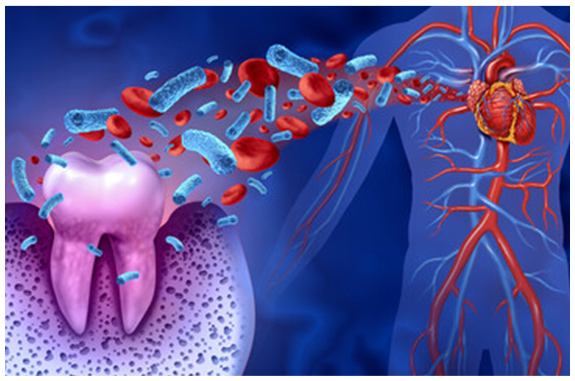

歯周病とからだの関係

歯周病は歯ぐきや血管、唾液を通して全身に歯周病菌を運んでしまい、その先でさまざまな疾患を引き起こすことがわかってきています。全身の健康のためにもしっかり治療し予防していきましょう。

脳梗塞

歯周病菌が歯ぐきから体内へ入り血流を阻害。脳梗塞を引き起こすこともあります。

心筋脳梗塞

体内へ入った歯周病菌が動脈硬化を引き起こすと心筋に血液が供給されにくくなります。

誤嚥性肺炎

歯周病の影響で誤って肺に入り込む細菌が増えると肺炎を起こしやすくなります。

糖尿病

炎症性物質が体内へ運ばれインスリンの働きを阻害。糖尿病が悪化します。

早産・発達不全

妊娠中の歯周病で早産や低体重児出産のリスクが高まる可能性が指摘されています。